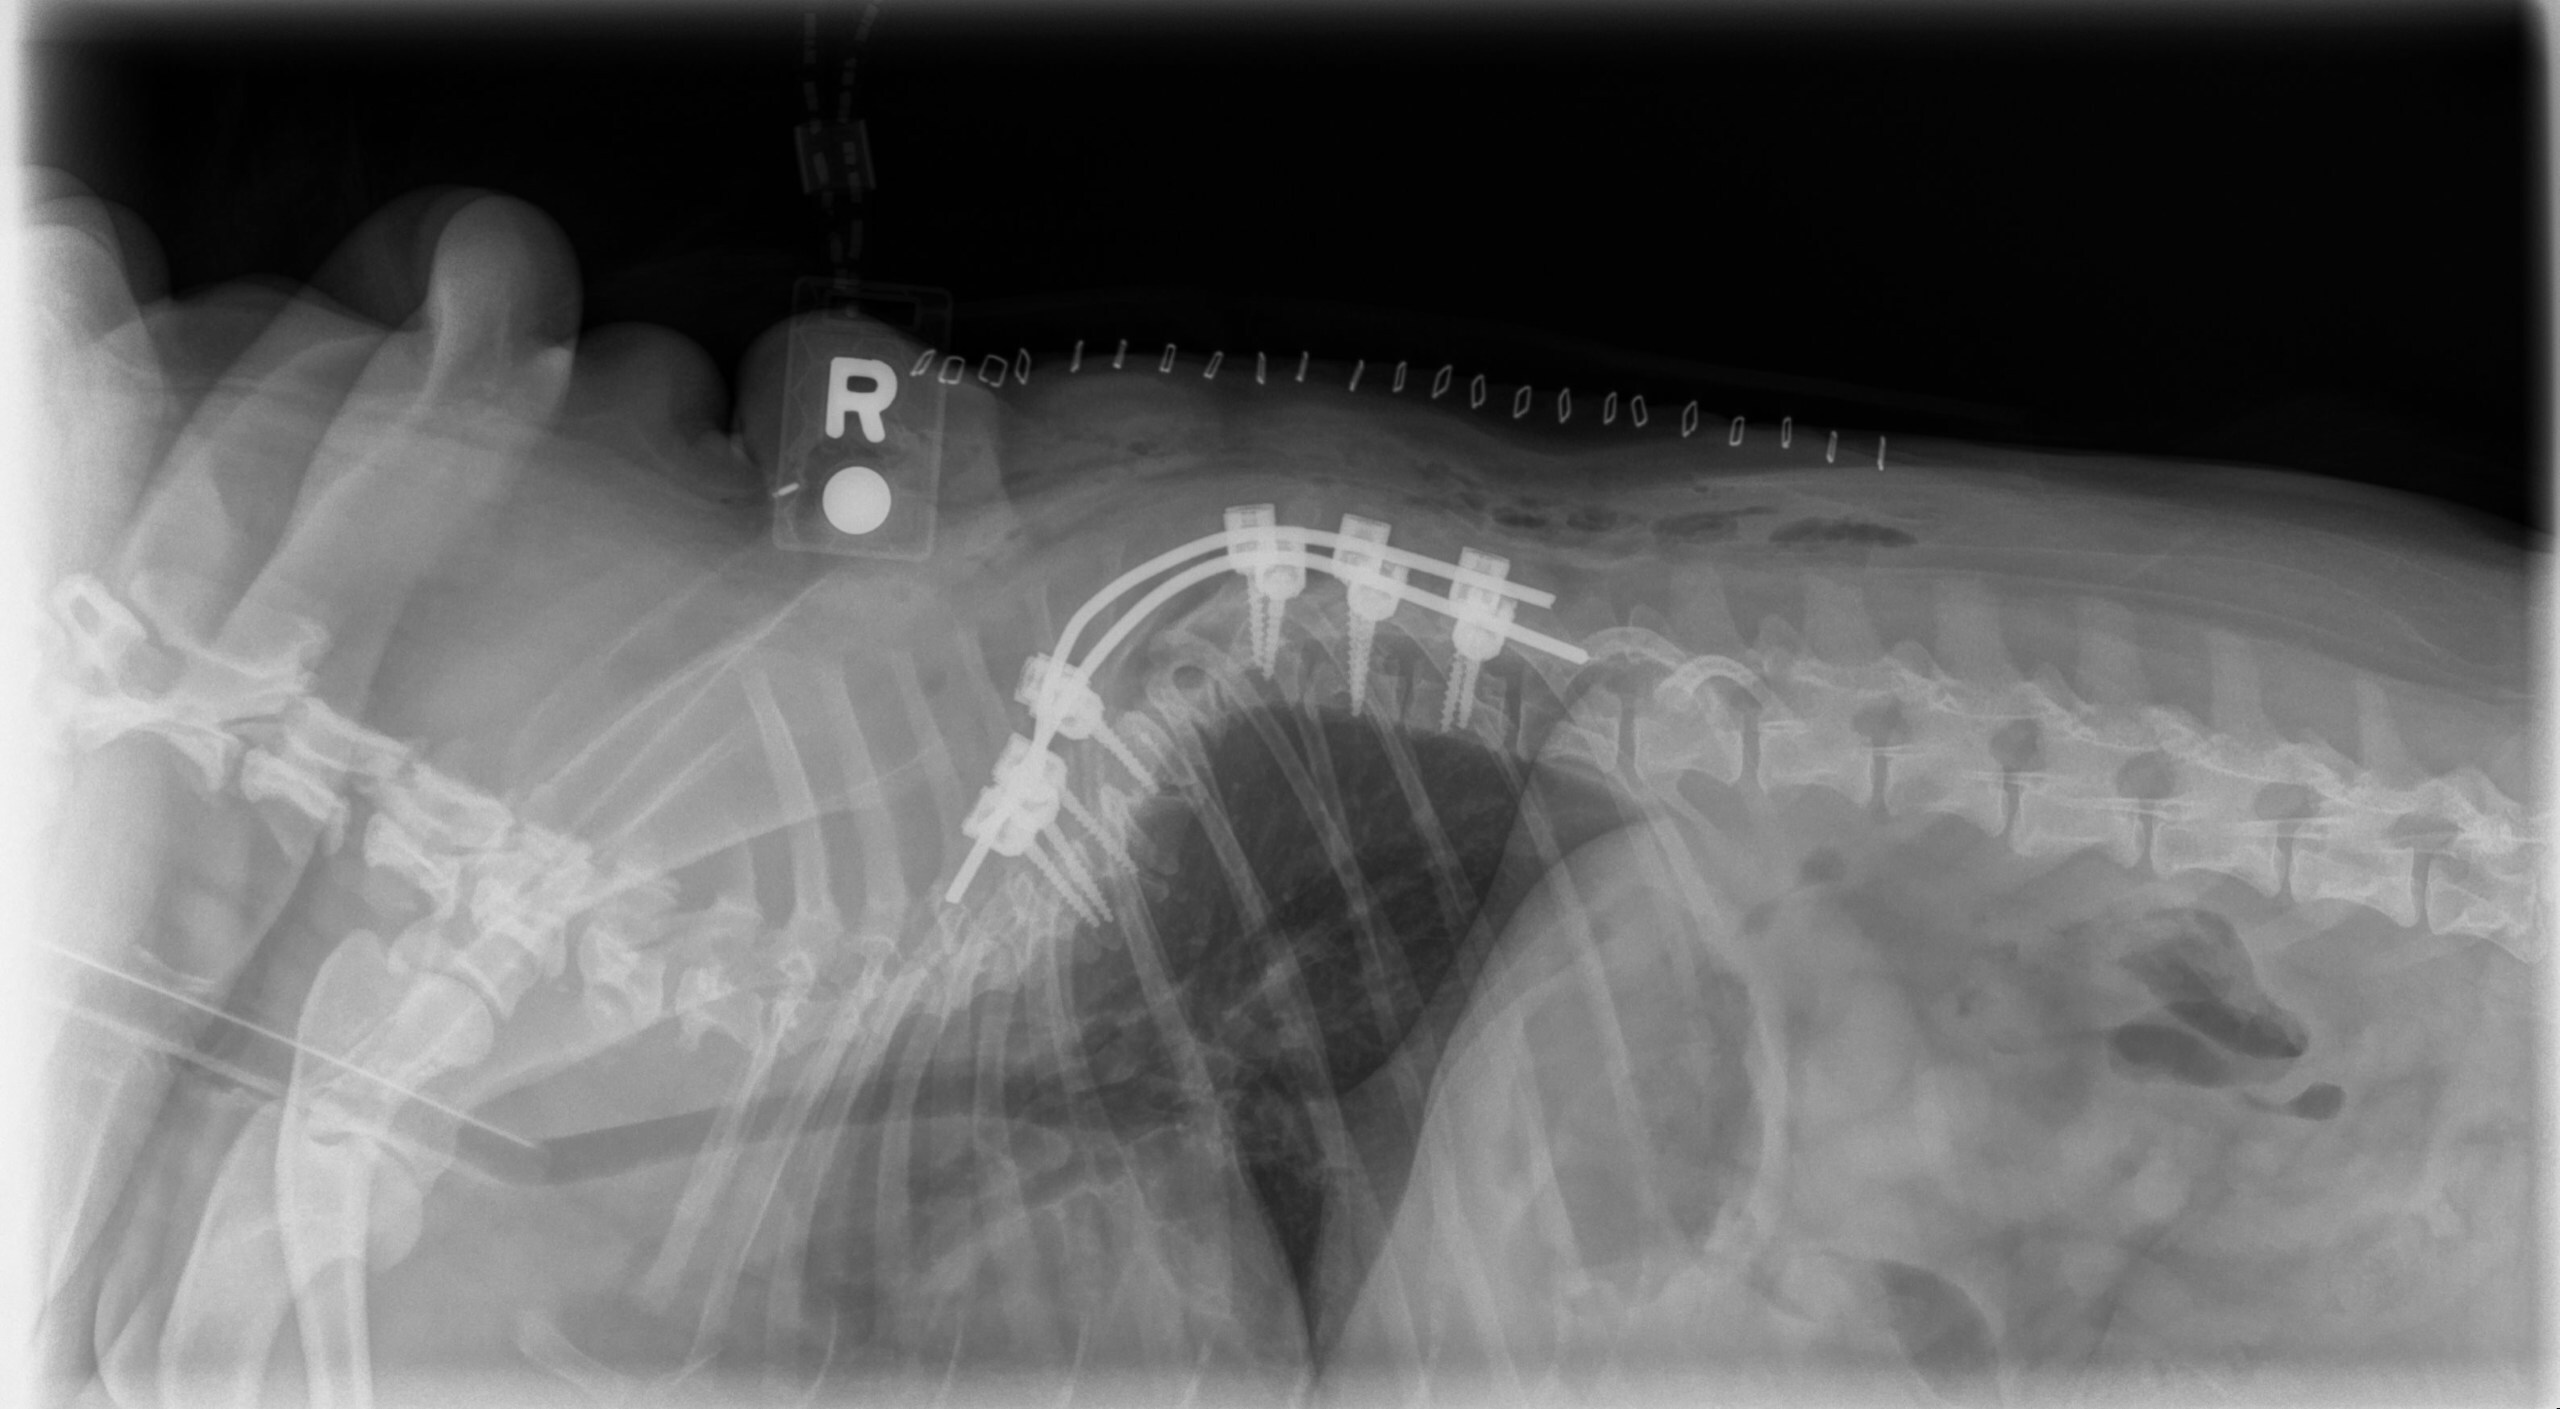

BOZEMAN, Mont., May 30, 2025 /PRNewswire/ — Bridger Veterinary Specialists (BVS) proudly announces the inaugural BVS Neurosurgery Summit — a premier, two-and-a-half-day event focused on advancing the field of veterinary neurosurgery. Tailored for specialists and residents within ACVIM…